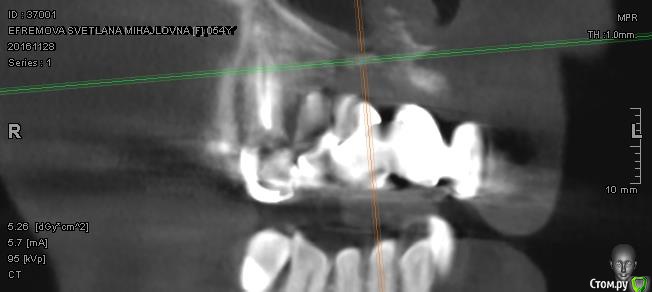

Сделала КТ. Прошу специалистов высказать свое мнение по новым снимкам. Область кости в районе единичек и двойки справа на верхней челюсти.

Можно ли уверенно сказать, что это остеомиелит? и какой вариант лечения посоветуете.

Забыла добавить. Острой боли нет и не было. На протяжении м.б. двух лет иногда бывали эпизоды небольшой ноющей боли, но я связывала это с простудой или переохлаждением. Иногда чувство щекотания или сверления в этой области. А вот последнее время эти симптомы участились.